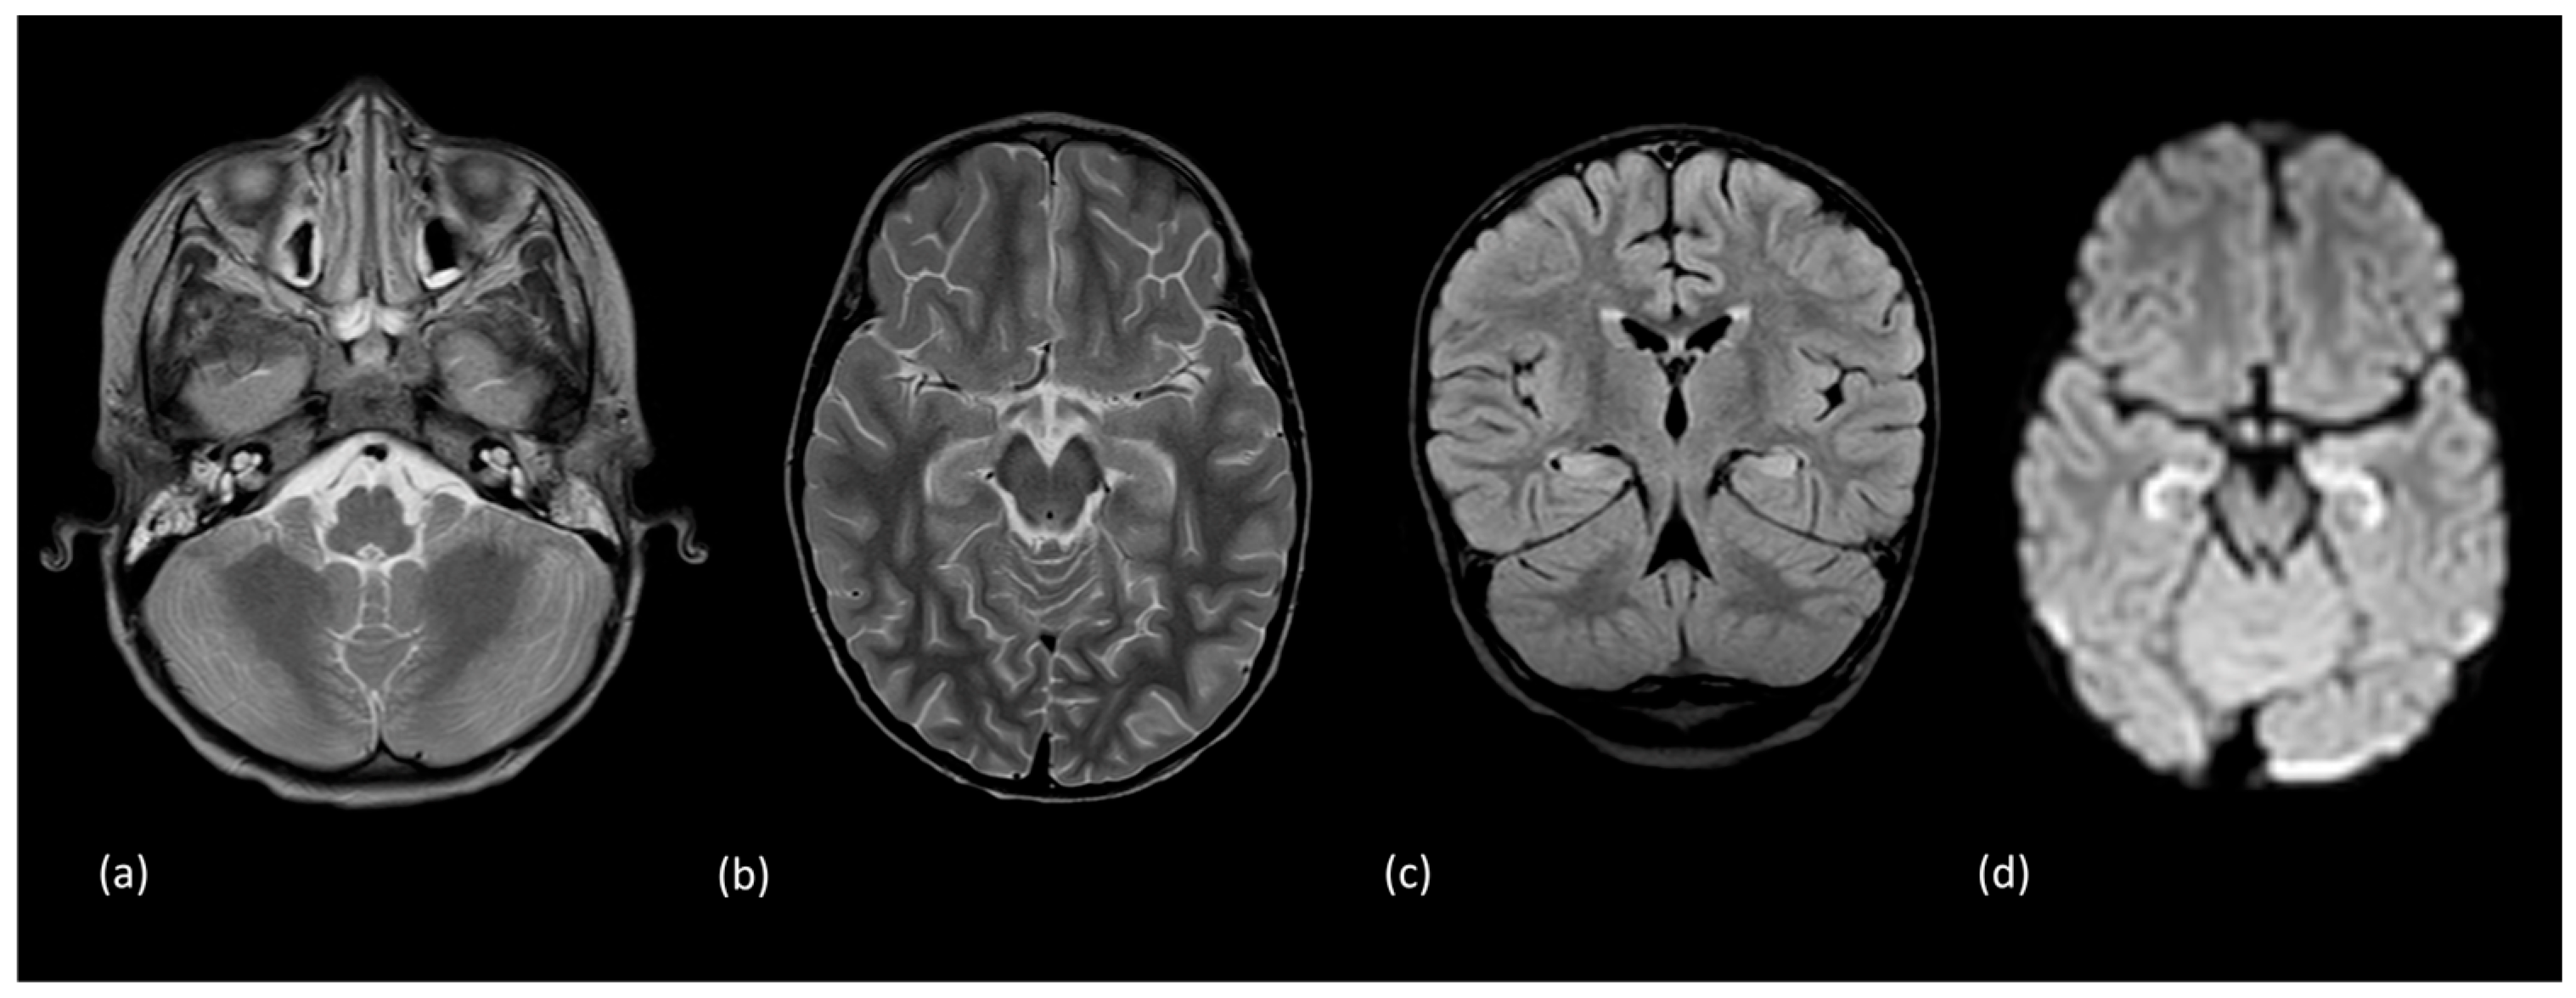

- Rivas-Coppola, M.S.; Shah, N.; Choudhri, A.F.; Morgan, R.; Wheless, J.W. Chronological Evolution of Magnetic Resonance Imaging Findings in Children With Febrile Infection-Related Epilepsy Syndrome. Pediatr. Neurol. 2016, 55, 22–29. [Google Scholar] [CrossRef] [PubMed]

- Culleton, S.; Talenti, G.; Kaliakatsos, M.; Pujar, S.; D’Arco, F. The spectrum of neuroimaging findings in febrile infection-related epilepsy syndrome (FIRES): A literature review. Epilepsia 2019, 60, 585–592. [Google Scholar] [CrossRef] [PubMed]

| FIRES | Acute phase: 2/3 unremarkable | N/A | N/A | |

| Acute phase: 1/3 with findings | temporal lobe, hippocampi, insular cortex: increased T2 and FLAIR signal | Leptomeningeal | ||

| Chronic phase | ventriculomegaly, mesial temporal lobe, cerebellum: atrophy | |||